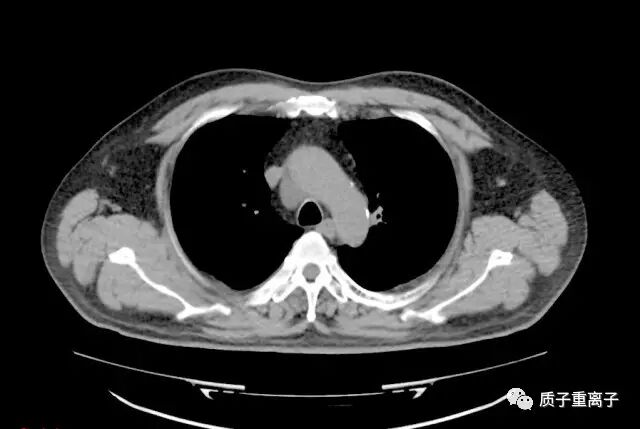

质子治疗一个月后复查:肿瘤较前明显缩小

质子治疗一个月前后对比:肿瘤由治疗前最大截面3.9×3.88cm缩小为2.13×2.48cm,治疗前肿瘤体积为44.56cm3,治疗一个月后为15.68cm3,体积缩小65%;